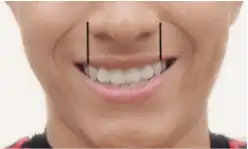

Nach der Funktionsabformung erstellt der Zahntechniker das Arbeitsmodell als Grundlage für die weiteren Arbeitsschritte. Es folgt die Anfertigung von Registrierschablonen (früher: Bissschablonen), mit deren Hilfe der Zahnarzt die Kieferrelationsbestimmung durchführt, die Okklusionsebene (Kauebene) festlegt sowie die Mittellinie und die Position der Eckzähne einzeichnet.[12] Es gibt zahlreiche Methoden zur Kieferrelationsbestimmung, z. B. die Stützstiftregistrierung. Hierzu werden mittels einer Hilfskonstruktion im Mund des Patienten die Bewegungen des Unterkiefers aufgezeichnet. Im Schnittpunkt der Bewegungslinien liegt die sogenannte habituelle Okklusion. Das ist diejenige Position des Unterkiefers, die der Patient in gewohnter Weise einnimmt (Normalbissstellung). Das Ausrichten von Wachswällen auf Bissschablonen ist ein weiteres Verfahren zur Kieferrelationsbestimmung. Durch Auftragen oder Reduzieren der Wachswälle kann der Patient unterschiedlich hoch zubeißen. In einer zu findenden entspannten Lage der Kiefer wird der Bissabstand ermittelt. Etwa zwei Millimeter geringer ist dann der ideale Kieferabstand bei zusammengebissenen (ersetzten) Zähnen. Insgesamt kann jedoch keine klare Empfehlung zur Wahl einer der Methoden abgegeben werden.[13] Die Einzeichnung der sogenannten Lachlinie in die Wachswälle lässt den Zahntechniker jenen Bereich erkennen, der beim Lachen sichtbar ist, denn der Prothesenkunststoff soll beim Lachen möglichst nicht sichtbar sein, sondern nur die Zähne. Lässt sich dies nicht vermeiden, stehen Kunststoffe in verschiedenen Rottönen der Gingiva zur Verfügung. Der Zahntechniker kann dementsprechend die Zähne aufstellen. Die Prothesenzähne sollen zudem mittig auf dem Kieferkamm aufgestellt werden, da durch eine exzentrische Aufstellung ebenfalls die Prothese ausgehebelt werden könnte.

Sollten keine Modelle oder Fotos der ursprünglichen, natürlichen Bezahnung vorliegen, werden die Prothesenzähne hilfsweise entsprechend dieser Konstitutionstypen bestimmt. Auch die Zahnform und -stellung von nahen Verwandten kann hilfsweise herangezogen werden. Nach dem von Albert Gerber für die Totalprothetik angegebenen embryo-genetischen Prinzip hat ein Mensch mit einer schmalen Nasenwurzel und einer breiten Nasenbasis einen im Vergleich zu den mittleren Schneidezähnen schmalen seitlichen Schneidezahn. Derjenige mit einer schmalen Nasenwurzel und -basis hat sowohl schmale mittlere als auch seitliche Schneidezähne und derjenige mit einer breiten Nasenwurzel und -basis besitzt sowohl breite mittlere als auch seitliche Schneidezähne.[17] Die Breite der Zähne und damit deren Größe kann aus dem Abstand der äußeren Nasenflügelbegrenzung („Eckzahnlinien“) bestimmt werden. Der Abstand ergibt die Gesamtzahnbreite der oberen sechs Frontzähne. Zahlreiche Wissenschaftler haben diverse Konzepte dazu entwickelt.[18] Zähne nutzen sich mit zunehmendem Alter ab (Abrasio dentium). Dies lässt sich durch ein entsprechendes Zuschleifen der Zähne altersentsprechend imitieren. Laien unterliegen oft dem Irrtum, dass die Zahnkanten der Frontzähne aufeinandertreffen. Im natürlichen Gebiss stehen die Oberkieferzähne jedoch vor den Unterkieferfrontzähnen (Overbite) und ermöglichen dadurch erst die Scherbewegung, die zum Abbeißen notwendig ist. Die Zahnkanten sind nicht gerade, sondern abgerundet. Die seitlichen Schneidezähne des Oberkiefers sind kürzer als die mittleren Schneidezähne. Nur bei einer Progenie (Vorstehen des Unterkiefers) werden die Zahnkanten aufeinandergestellt („Kopfbissstellung“). Farbe, Form und Stellung der Zähne sollen möglichst ein natürliches Aussehen bewirken.

Bestimmung der Eckzahnlinien

Bestimmung der Eckzahnlinien -